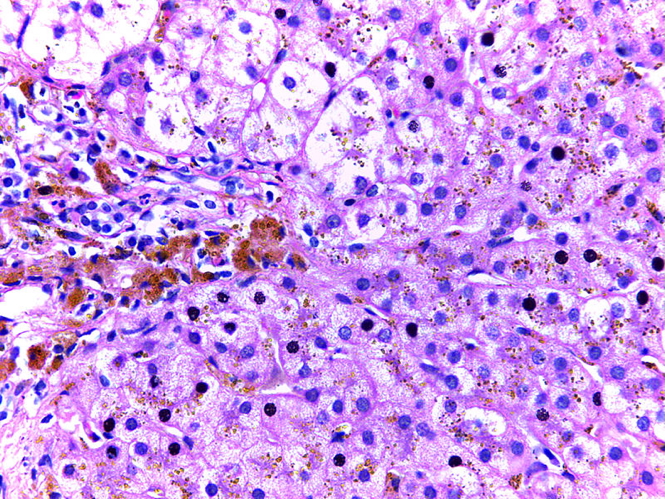

- Liver biopsy (rarely needed now; used to confirm iron overload)

- Liver → fibrosis → cirrhosis

- Leads to iron accumulation in parenchymal tissues.